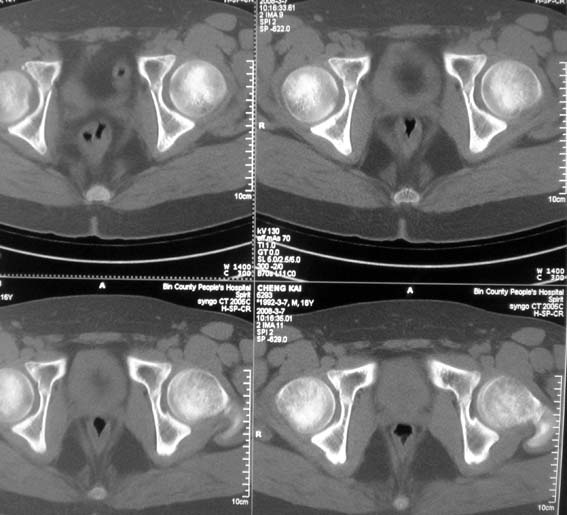

男,16岁,髋部疼痛,发育延迟。

考虑:双侧髋臼发育不良性骨病。

双侧髋臼发育不良性骨病

双侧髋臼发育不良性骨病.股骨头早期坏死?

双侧髋臼发育不良性骨病(髋臼窝变浅,髋臼内上缘关节面毛糙)。

考虑:双侧髋臼发育不良性骨病